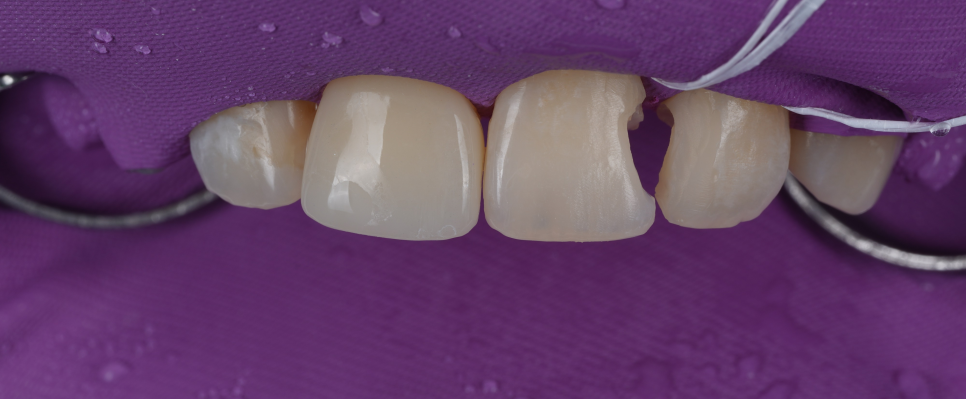

레진은 수분에 약하기 때문에 방습을 철저히 해야 해요.

그래서 중간중간 격리가 잘 되고 있는지 확인을 해가며 작업을 했고 큐레이를 이용해 남아 있는 충치 및 레진은 없는지 꼼꼼하게 확인까지 도와드렸죠.

입 천장 쪽에서 확인한 모습

기존 레진을 다 제거한 뒤 접착층을 만들고 치아색과 투명도가 비슷한 레진을 여러 층으로 쌓았어요.

한 층 붙이고 굳히고 또 붙이고 굳히고.... 정성스레 겹겹이 쌓아 공들여 작업해야 돼요.